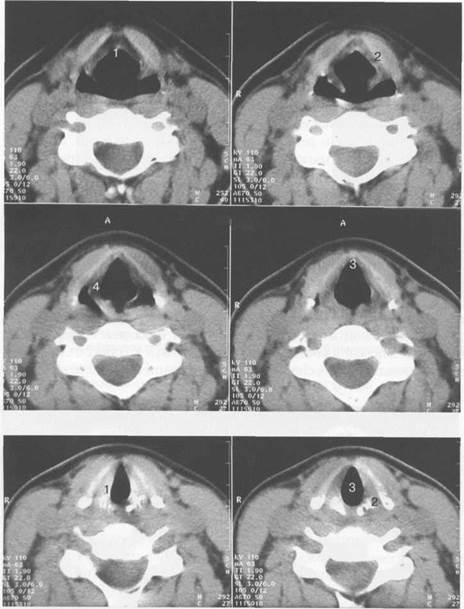

На нижерасположенных сканах (рис. 6.4) отображаются желудочковые и голосовые складки, передняя комиссура, пластинки щитовидного и перстневидного хрящей. Голосовые складки имеют однородную структуру. Ширина их в передних отделах составляет 2 мм, а в задних отделах достигает 9 мм. Свободные края голосовых складок симметричны. В передних отделах денситометрическая плотность голосовых складок около 20 Н U, в задних достигает 70 HU.

Рис. 6.4. КТ гортани